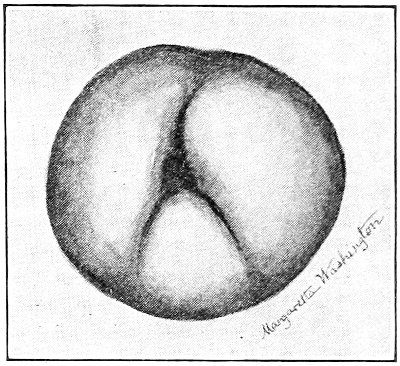

Cysts of the gland may be unilocular if formed at the expense of a single lobule of the gland, or multilocular if several lobules enter into their formation. These cysts may attain the size of the fetal head (Fig. 18).

Cysts of the gland or of the duct are formed by retention of the cyst-contents. The retention is due to occlusion of the duct, usually the result of inflammation. In some cases the duct remains pervious, and the retention is due to the altered character of the secretion of the gland, which becomes too viscous to pass, except under unusual pressure, along the duct.

These cysts contain clear yellow or chocolate-colored 42 fluid. The diagnosis of cyst of the vulvo-vaginal gland is usually not difficult. If we are in doubt in regard to the fluid character of the tumor, this may be determined with the exploring-needle.